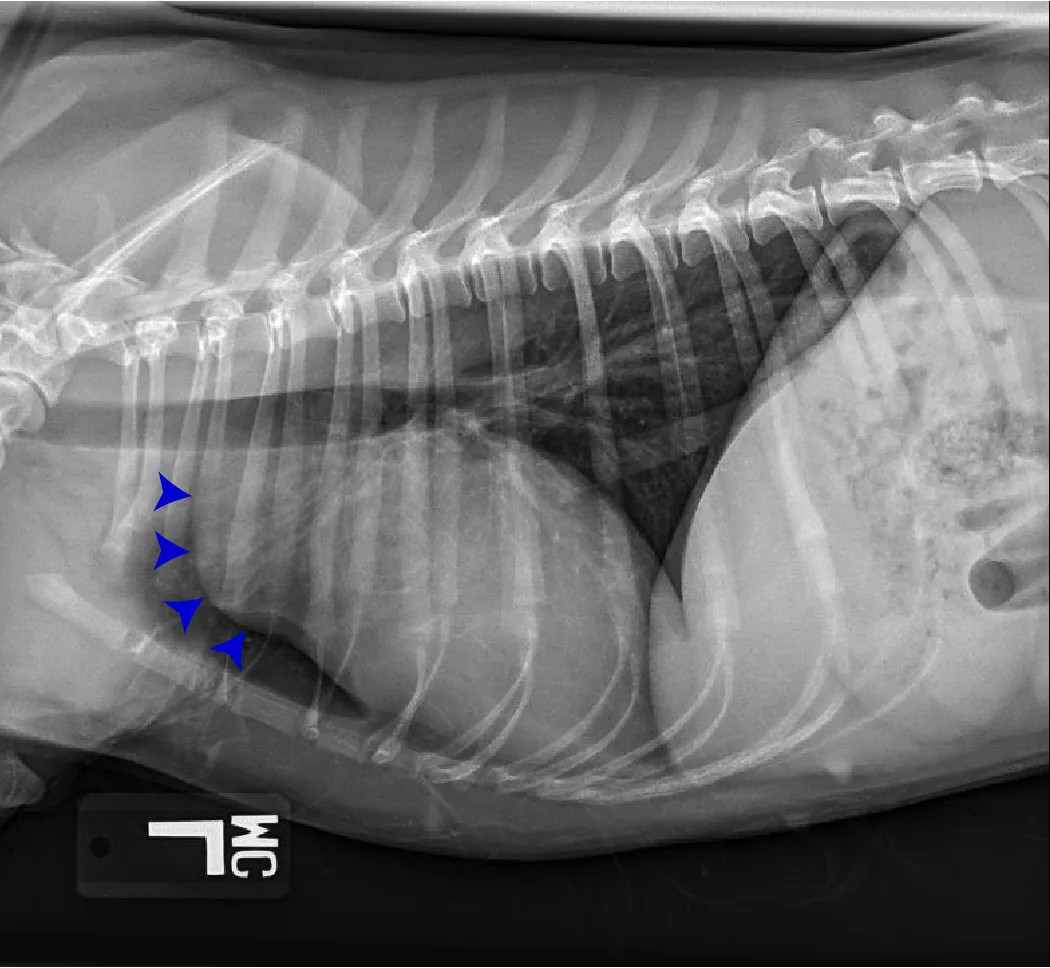

Common congenital heart diseases in dogs include pulmonic stenosis, patent ductus arteriosus, and subaortic stenosis. In addition to providing valuable information regarding the pulmonary parenchyma and vasculature, thoracic radiography may provide clues into which type of congenital heart disease is present. For example, a dog with left-sided cardiomegaly and a bulge in the ascending aorta raises suspicion for subaortic stenosis (Figure 10), whereas a dog with right-sided cardiomegaly without an MPA bulge raises suspicion for tricuspid valve dysplasia (Figure 11). Qualitative assessment of individual cardiac chambers with thoracic radiography can be an inaccurate method for diagnosis of congenital heart disease and right-sided heart enlargement in dogs. Definitive diagnosis is achieved with echocardiography.17,18 An objective parameter (ie, vertebral right heart index [VRHi]) could be a useful tool for accurate radiographic determination of right-sided cardiomegaly, although studies are needed to evaluate the influence of left-sided heart enlargement and individual breed differences in the normal range, as well as breed-specific cutoffs used for this parameter (Figure 12).19

FIGURE 12 Representation of the VRHi with a value of 2.9 in a dog with a normal cardiac silhouette (left), and a dog with pulmonic stenosis and right-side heart enlargement with a VRHi value of 3.6 (right). Using the right lateral projection for measurement, a value ≥3.5 detects right-sided heart enlargement with a sensitivity of 68% and specificity of 86%.16 Images courtesy of Federico Villaplana Grosso, DACVR, DECVR, and Bruna Del Nero, DACVIM (Cardiology). Illustration courtesy of Jose Narvaez Perez